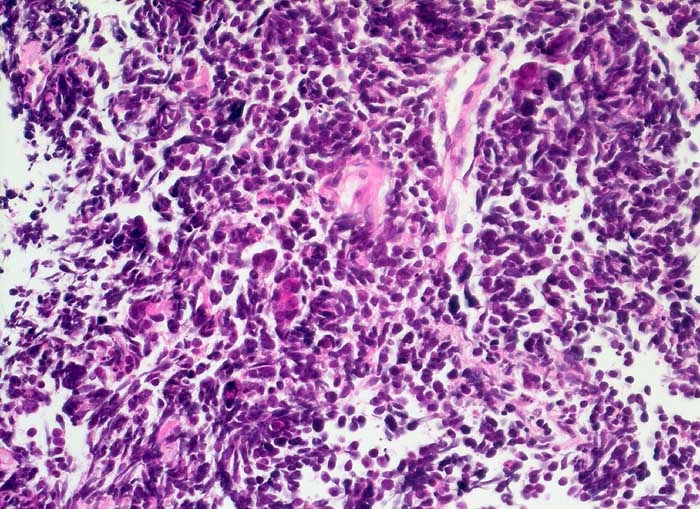

Kleinzelliges Karzinom und reaktive Epithelatypien

Die Bronchialschleimhaut im Randbereich von Karzinomen oder über submukös wachsenden Tumoren kann erhebliche reaktive Atypien oder eine Plattenepithelmetaplasie aufweisen. In solchen Fällen besteht die Gefahr, dass einzeln liegende oder schlecht erhaltene Karzinomzellen inmitten der eindrücklichen reaktiven Epithelatypien übersehen werden. Im vorliegenden Falle eines kleinzelligen Karzinoms hätten reaktive Atypien des Bronchialepithels zur Fehldiagnose eines Adenokarzinoms verleiten können, zumal die unscheinbaren Karzinomzellen beim Screenen übersehen wurden.